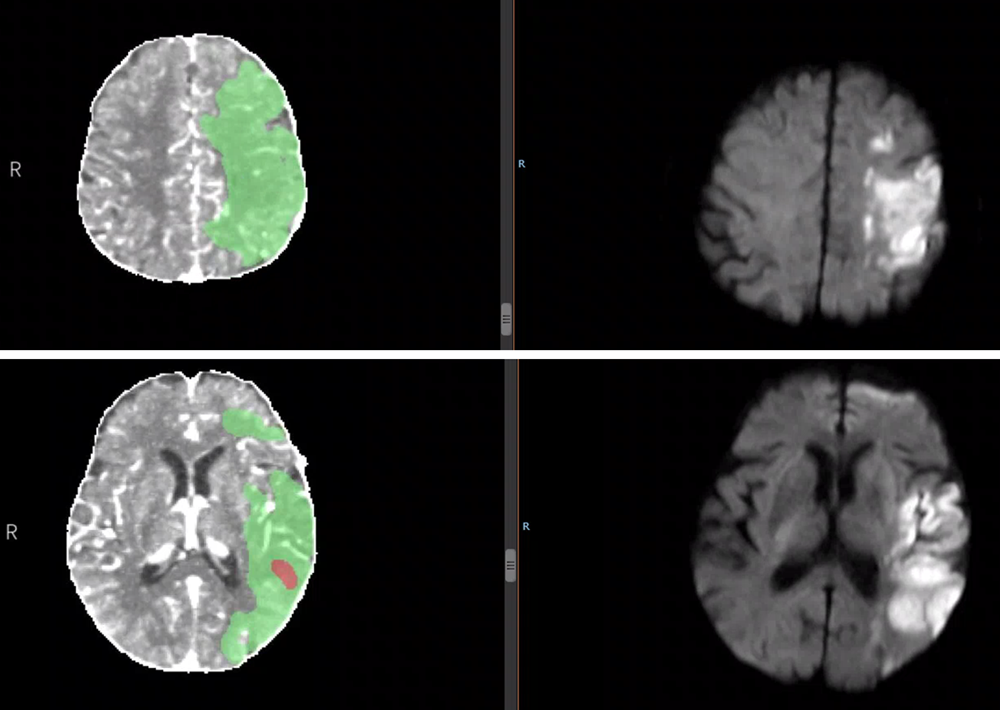

CTP灌注成像:红色区域梗死核心,绿色区域为缺血半暗带

左侧:溶栓前CTP灌注成像显示梗死核心(红色)与缺血半暗带(绿色)

右侧:溶栓后磁共振DWI显示最终梗死范围(高亮区)